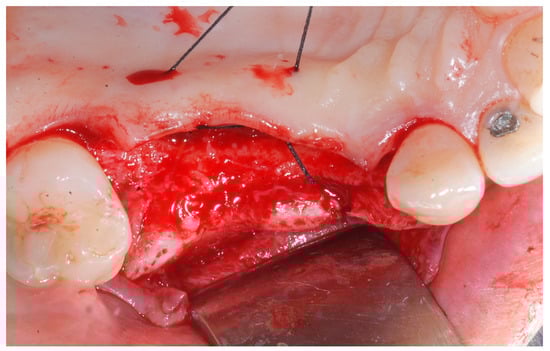

Six months following augmentation, re-entry surgery was carried out to uncover the implants and connect the healing abutments. Following chlorhexidine rinses and the injection of local anesthetics, crestal incisions as well as releasing incisions along the same lines as the ones during augmentation surgery were performed. Mucoperiosteal flaps were raised in order to visualize the augmented bone volume (Figure 9 and Figure 10).

Figure 9. Reopening surgery showing no membrane residues and obtained buccal bone thickness.

Medicina 61 01814 g009

Figure 10. Reopening surgery showing no membrane residues and obtained buccal bone thickness.